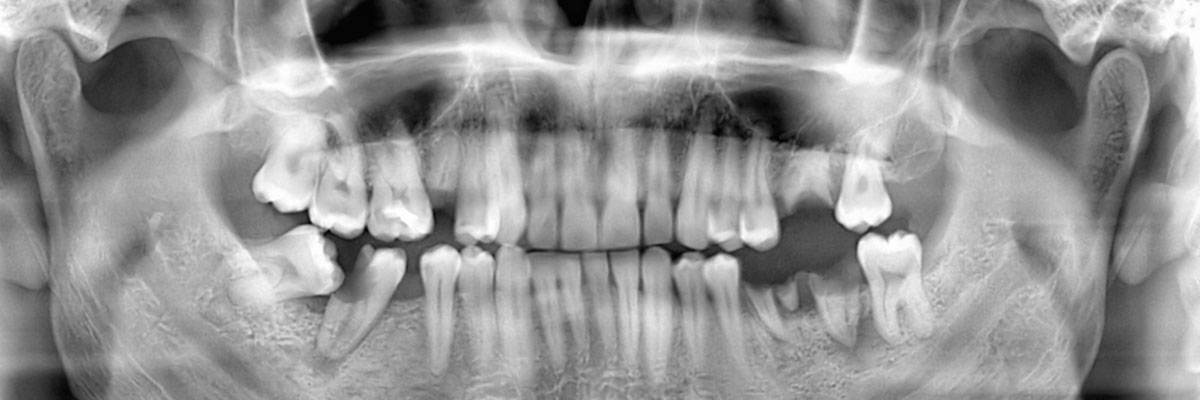

We recommend that you call 516-301-9038 and schedule an appointment with our dental office as soon as your tooth has either fallen or been knocked out. During your appointment, we will examine your gums, take X-rays, and make a recommendation as to which tooth replacement option will be best suited for your needs. Acting on this quickly will help in restoring your appearance and oral health.